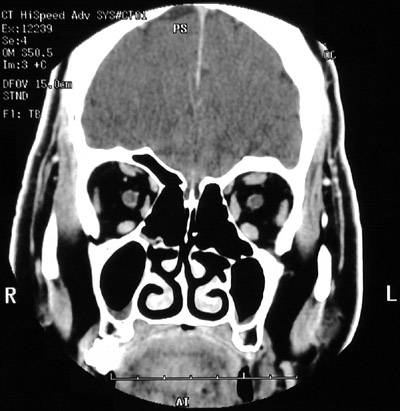

This is a normal sinus CT scan demonstrating structures in the orbit, including optic nerve and superior rectus muscle and superior oblique muscle and medial rectus muscle and inferior rectus and inferior oblique muscles and lateral rectus muscle in the anterior skull.